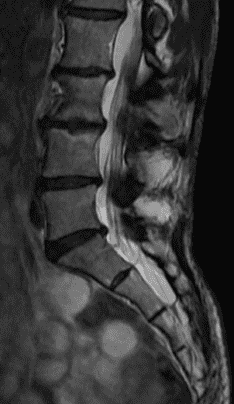

- Estenose do canal vertebral lombar. Neste tipo de afecção, o estreitamento ocorre na parte da coluna vertebral onde está a região inferior da coluna. É a forma mais frequente de Estenose do conduto vertebral.

- Ressonância Magnética (RM)